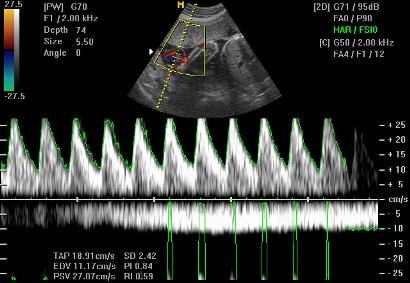

Со доплер ултразвучниот преглед, срцевата акција на бебето може да се регистрира уште во 6. гестациска недела, а најдоцна до крајот на седмата недела. Доколку се регистрира срцева работа во овој период, за понатаму постои голема веројатност дека ќе имате нормална бременост. Во шестата недела бебешкото срце работи со фрекфенција од околу 95 – 110 удари во минута, а во следните 3 недели фрекфенцијата расте на 150 – 170 удари во минута. Мерењето на срцевата работа на плодот дава податоци за неговиот развој и може да предупреди за можни компликации во текот на бременоста. Покрај срцевата работа, со доплер се испитува и папочната артерија, со мерење на протокот и отпорот во артеријата која се наоѓа во папочната врвка. Овие параметри се показател за уреден раст на плодот и нормална функција на постелката (плацента). Се испитуваат уште и големите крвни садови (аортата и шупливите вени) и мозочните артерии на плодот.

Вообичаено доплерот е инкорпориран во ехо апаратите, така што не мора да се преместувате за преглед со доплер. Доплер прегледот може да се врши со абдоминална или со вагинална сонда. На странскиот пазар се присутни и портабл апарати со кои мајката може сама да го слуша срцето на своето бебе. Погледнете го видеото и слушнете како звучи срцето на бебето на доплер.